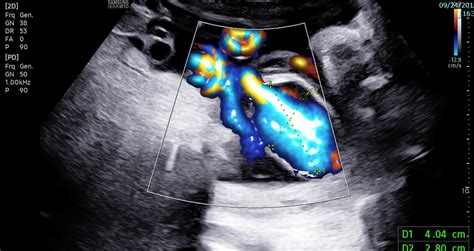

Detection usually occurs during the second or third-trimester anatomy scan. Sonographers look for a fluid-filled, cyst-like structure within the fetal abdomen that shows blood flow when color Doppler ultrasound is applied. Because the structure is vascular, it is easily distinguishable from other fluid-filled cysts (like those in the gallbladder or bowel) once the appropriate imaging techniques are utilized.

• Doppler Flow Studies: These studies measure the velocity and pattern of blood flow through the varix to check for turbulence or restricted flow.

Detection Method Color Doppler Ultrasonography